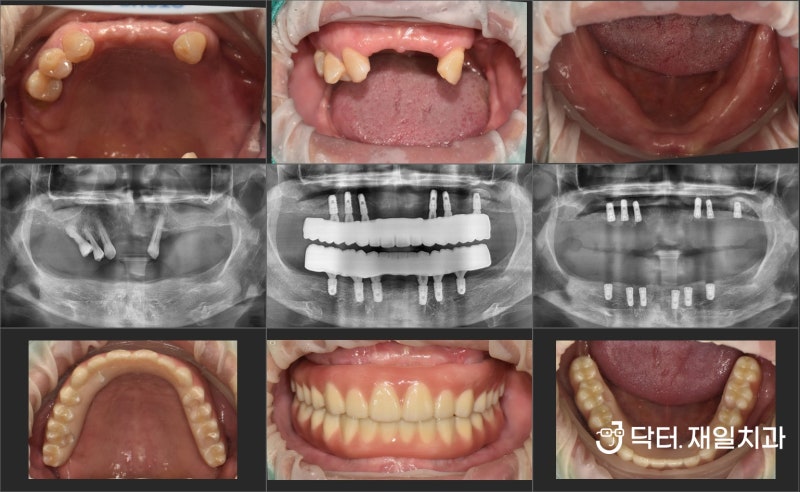

2022.09.02 / 시술 전 파노라마

오늘은 무치악 임플란트/전악 임플란트/전악 임플란트/성내동 임플란트를 소개합니다. 임플란트 의치 또는 전체 치과 임플란트 치료. 위의 이미지는 이에 대한 예입니다.

2022.09.02 / 치료전 구강사진은 보통 치아가 조금 남아있지만 윗니가 좋지 않아 전체 치아를 발치해야 하는 경우가 많고 고정식 임플란트 틀니 매직4도 사용이 가능합니다.

2022.09.06 / 상악 수술 후 파노라마 턱의 경우 모든 환자에게 매직4 고정 임플란트 의치용 임플란트 6개를 식립합니다. 일반 임플란트와 마찬가지로 magic4는 원할 경우 부비동 거상술과 함께 사용할 수도 있습니다. 골이식의 경우 어금니 측면 치은골이 너무 적으면 측면거상법을 이용하여 더 많은 양의 골이식재를 식립할 수 있다. 임플란트 탐색? 많은 사람들이 내비게이팅 임플란트에 대해 들어봤을 것입니다. 전체적인 경우로 보면 비용적인 요소가 있기 때문에 내비게이션 임플란트를 특별히 추천하지는 않습니다. 충분한 경험을 가진 구강외과 전문의에게 시행된다면 이러한 추가 비용 없이 성공적인 수술이 가능합니다. 일반적인 임플란트 수술과 적은 수의 보형물을 이용한 전체 임플란트 수술은 단순히 갯수로 판단하기에는 쉽지도 어렵지도 않습니다. 가능합니다~ 2022.09.06 / 상악동 수술 후 CT (상악동 설명사진 사진예시) 수술 후 CT에서 보듯이 상악동 거상은 측면거상법과 뼈이식을 이용하여 돔형태로 할 수 있습니다. 2022.10.04 / 하악 수술 후 파노라마 보통 위턱과 아래턱에 매직4 풀 임플란트 수술을 비슷한 시기에 완료하고자 하는 경우 2차 진정 후 약 한 달 후에 시행하게 됩니다. 원데이 임플란트? 원데이임플란트라는 말도 있는데 하악 골밀도가 단단한 경우에는 원데이임플란트도 가능합니다. 오후에는 PMMA를 임시치아로 사용하는데 안전을 최우선으로 하고 환자분께서 원하신다면 임시틀니로 취급하여 자연스럽게 틀니를 만들어 드립니다. 오늘 제가 말씀드리는 환자분이라면 원데이 임플란트로 수술 직후 인상채득이 가능하여 빠르게 씹을 수 있습니다. 임플란트는 하루에 한두개 심는것만큼 좋지는 않지만 전체적인 상황에서 원데이와 같은 임플란트를 하는 경우가 상당히 많습니다. . 밑면. 시간이 지남에 따라 경화됩니다. 뼈가 전혀 없는 상태에서 뼈이식을 잘하면 내 뼈가 되어 임플란트가 잘 버틸 수 있을 정도로 튼튼해집니다. 신비로움이 느껴지고 인체가 정상인 것 같습니다. 아무것도 아닌 것 같은 느낌? ㅎㅎ 2023.02.10 / 완전치료 파노라마매직4 전체 임플란트 치료기간 일반적으로 발치 후 즉시 식립을 하는 경우 총 증례 수는 모두 4~5개월 정도의 기간을 고려하는 것이 가장 좋습니다. 임플란트 부작용 예방 임플란트 부작용 관리 임플란트주위염! 관리가 잘못되었을 때 발생할 수 있습니다. 그렇더라도 초기에 예방할 수 있도록 정기적인 검진을 통해 잘 확인하는 과정이 필요합니다. 오늘은 저희 무치악임플란트/전악임플란트/전악임플란트/수면마취가 많은 길동임플란트/성내동임플란트가 좋은곳 제일치과의 고정임플란트틀니 매직4 치아를 건강하게 지켜주고 잘먹게 해주는 두려운 분들은 치과진료, 진정치과의원에서 치과 수면치료로 편안한 경험을 하실 수 있으며, 이후 사랑니 등을 과감하게 뽑을 수 있도록 도와드립니다. 치과에서 행하는 모든 치료가 가능합니다. 이것으로 닥터자일리톨의 두 번째 이야기를 마칩니다! 건강하고 행복한 하루 되세요~ 강동구 올림픽로 796 제일치과의원 강동구 2층